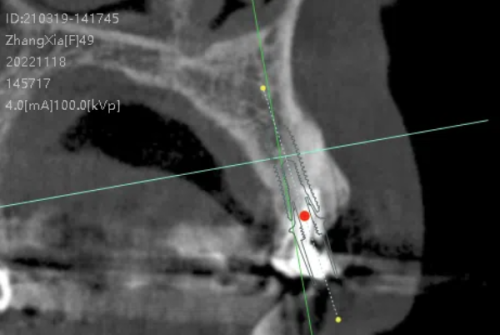

大同金冠口腔门诊部开展的牙科项目极为丰富。种植牙方面,采用3D微创种植技术,能够精细定位种植位置,减少手术创伤和修复时间,还提供多种种植体选择,包括经济实惠的韩国进口种植牙和功能性较强的瑞士士卓曼ITI、瑞典nobel诺贝尔高端种植牙。牙齿矫正项目中,有隐形矫正、金属托槽矫正、陶瓷托槽矫正等多种方式可供选择,满足不同患者的需求。此外,还涵盖洗牙、龋齿、补牙、涂氟、拔智齿、美容冠、预成冠、奶瓶龋、牙贴面、地包天、根管治疗、骨性龅牙、烤瓷牙冠、全瓷牙冠、嵌体修复、皓齿美白、儿童龋齿、窝沟封闭、凸嘴矫正等众多项目,为广大患者提供一站式的口腔服务体验。